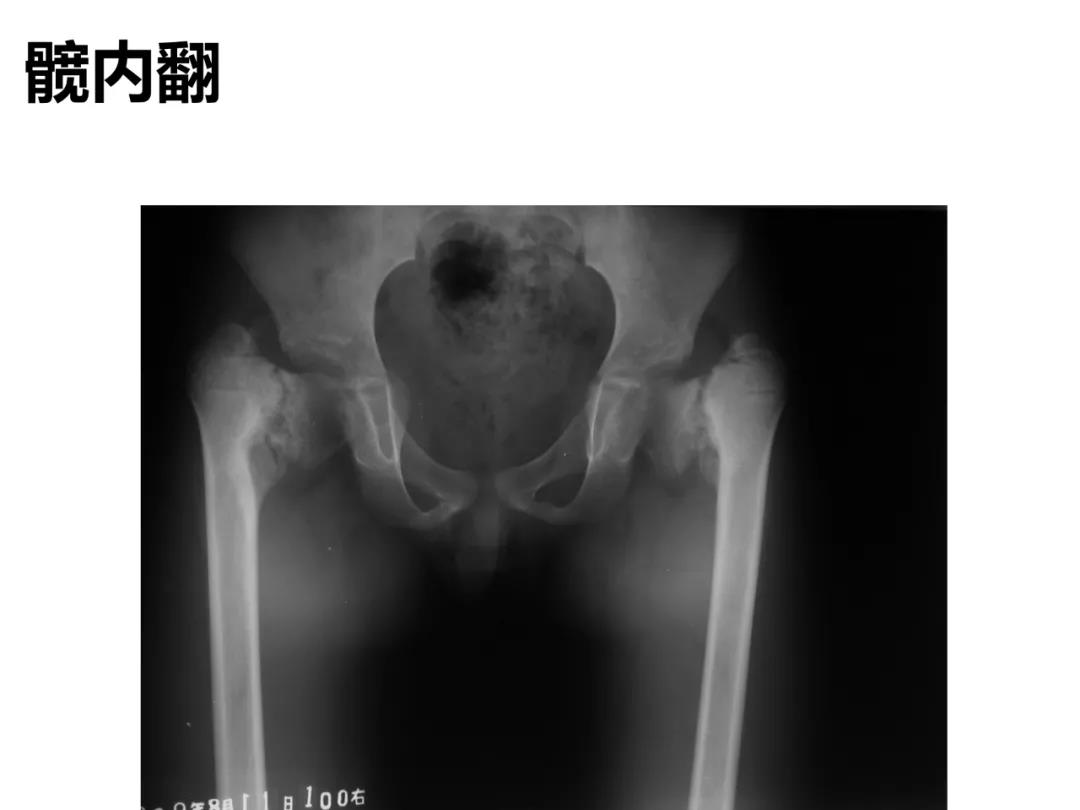

小儿骨科X线片汇总,临床读片宝典!